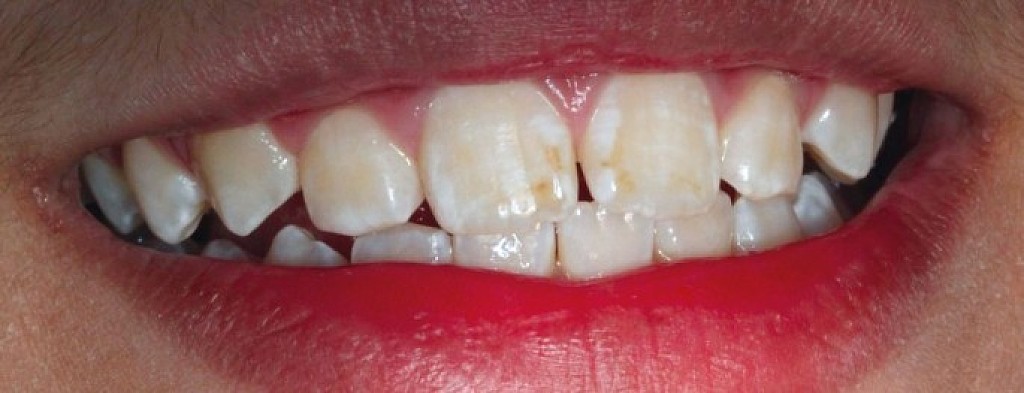

What Is Enamel Hypoplasia?

Enamel is the hard, protective outer layer of your teeth. Enamel hypoplasia is a defect of the enamel that only occurs while teeth are still developing. Still, it can affect both baby teeth and permanent teeth. The condition results in thin enamel, which makes your teeth vulnerable to dental decay.

The visual signs of enamel hypoplasia include white spots, pits, and grooves on the outer surface of the teeth.

pits, tiny groves, depressions, and fissures

white spots

yellowish-brown stains (where the underlying layer of dentin is exposed)